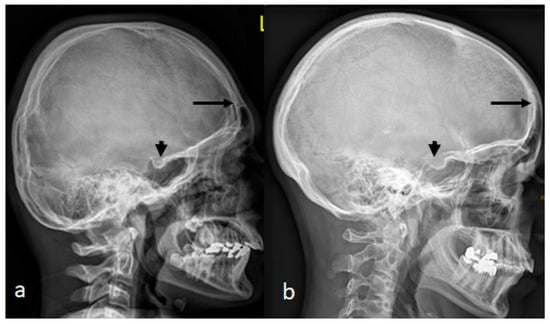

A 7-year-old boy with West syndrome associated with hyperkinetic disorder was referred to our department because of ligamentous hyperlaxity and flat foot. Clinical examination showed growth deficiency (10th percentile). Surprisingly, he manifested an abnormal cranial phenotype almost typical for his mother. Palpation of his skull showed a bony ridge over the metopic suture, associated with an unusual bulge over the mid-sagittal suture. Bilateral bony ridges over the squamosal sutures were well delineated. Palpation of his 35-year-old-mother’s skull showed a prominent bony bulge over her sagittal suture. AP skull radiograph of a 7-year-old boy with West syndrome showed facial asymmetry with early closure of the metopic suture (arrow head) similarly the coronal as well as the sagittal sutures showed post-closure sclerosis (Figure 1a). A 3D reformatted frontal cranial CT of a 35-year-old mother clearly showed the closure of the metopic (arrow) and the sagittal sutures causing a mid-sagittal bony bulge (red-arrow) (Figure 1b). A 3D reconstruction CT scan of the 7-year-old-child with mild flexion of the skull showed early closure of the metopic suture (arrow) (a). A 3D reconstruction CT scan showed early closure of the squamosal sutures (arrow), pressing the brain contents upward, causing the development of a prominent bulge at the top of the mid-sagittal sutures two arrows (Figure 2b). Another 3D reconstruction CT scan confirmed the bilateral closure of the squamosal suture (arrow head). The vertical arrow showed abnormal bulging of the vertex secondary to bilateral pressure exerted by the squamosal sutures (c).

Figure 2. (a) A 3D reconstruction CT scan of the 7-year-old-child with mild flexion of the skull showed early closure of the metopic suture (arrow). (b) A 3D reconstruction CT scan showed early closure of the squamosal sutures (arrow), pressing the brain contents upward, causing the development of a prominent bulge at the top of the mid-sagittal sutures two arrows. (c) Another 3D reconstruction CT scan confirmed the bilateral closure of the squamosal suture (arrow head). The vertical arrow showed abnormal bulging of the vertex secondary to bilateral pressure exerted by the squamosal sutures.